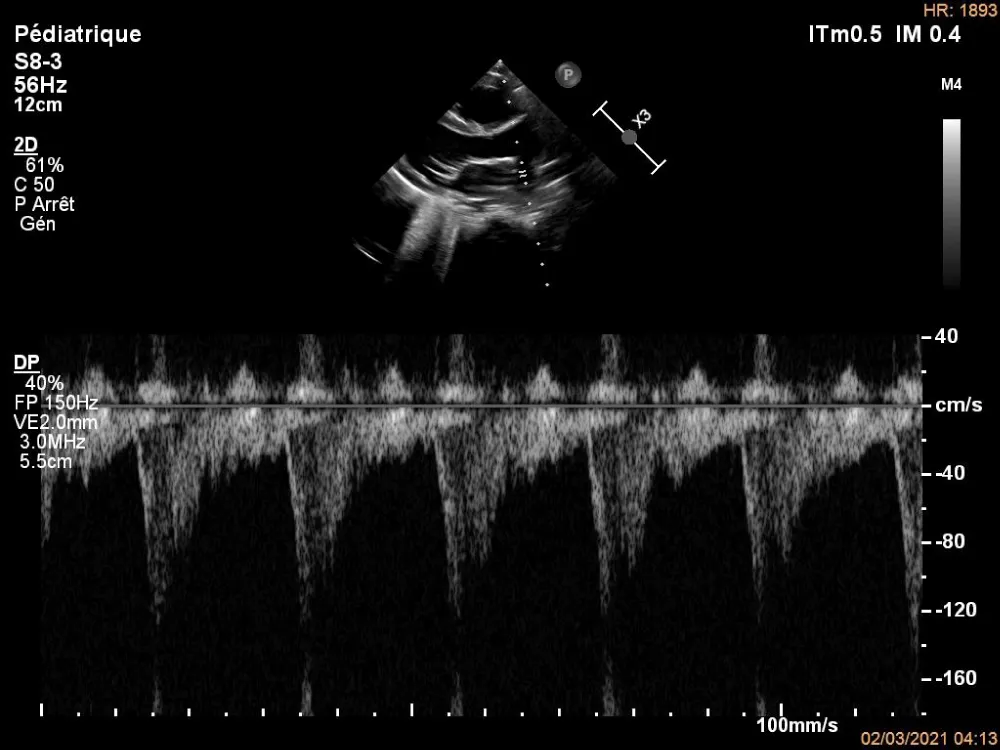

The electrocardiogram showed bi-atrial and left ventricular hypertrophy. On frontal telethorax, cardiomegaly with a supra-diaphragmatic peak, a right inferior arch overhang, and peri-hilar vascular overload, predominantly on the right. Cardiac ultrasound revealed a situs solitus heart with levocardia. The aorta normally emerges from the left ventricle, without obstruction. After a few centimeters, it gave way to a right pulmonary artery that filled correctly in systole without obstruction (Figures 1,2). The left pulmonary artery arises directly from the right ventricle. All cardiac cavities are dilated—suprasystemic pulmonary hypertension with ostium secundum-type atrial septal defect with right-to-left shunt. Cardiac angioscan confirmed the diagnosis, showing a 13 mm right pulmonary artery arising from the aorta. The left pulmonary artery arises directly from the right ventricle and measures 9.73 mm, with a functional pulmonary valve (Figures 3,4). Biological tests revealed microcytic hypochromic anemia at 9.3 g/dl. Medical treatment was based on furosemide, captopril, and spironolactone. A surgical cure after catheterization with reimplantation of the right pulmonary artery was indicated. The child died before surgery.

Figure 2: Pulsed Doppler echocardiography on the right pulmonary artery.